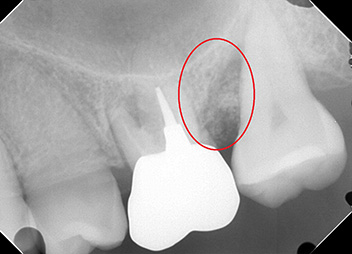

リグロス(歯周組織再生療法)の症例

年齢/性別が表示されたボタンを押すと、下部にスクロールして症例の画像と詳細をご覧になれます。